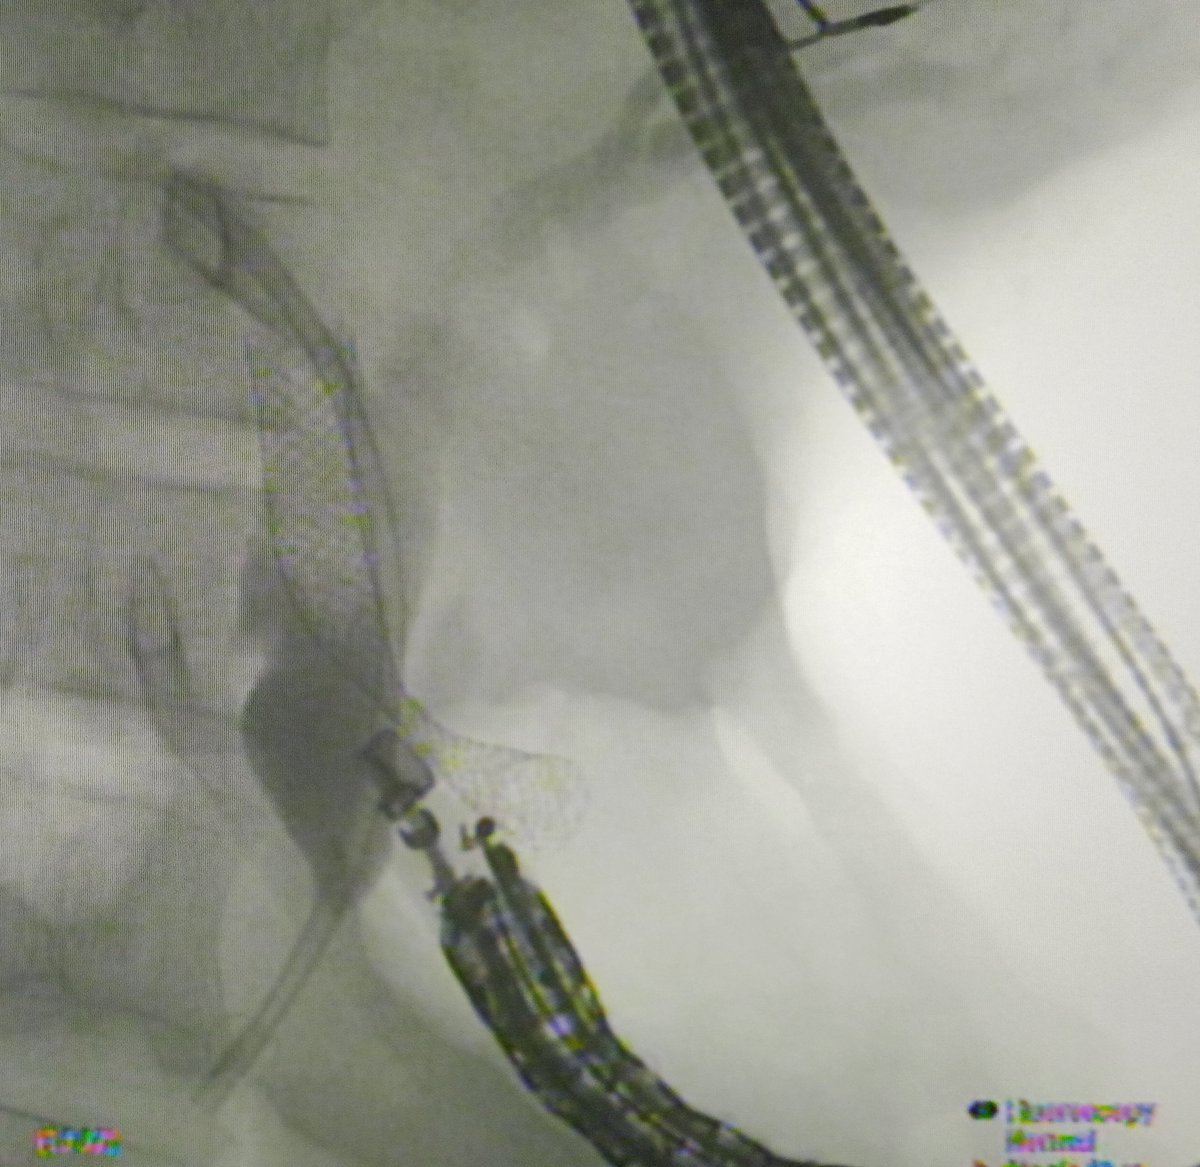

Hilar stricture ERCp♟♟♟game 👉 Understand anatomy 👉 Image 🎯 drainage 👉 Concept of draining 50% for palliation is outdated 👉 Liver sectoral drainage/single or multiple stents>unilat/bilat 👉 ucSEMS⏩SIS(open cell, laser cut stent)>SBS>plastic stents (Johlin stent)

Anatomical concepts & technical considerations for #ERCP in patients w/ malignant hilar biliary obstruction https://t.co/3nBDbbFsgV